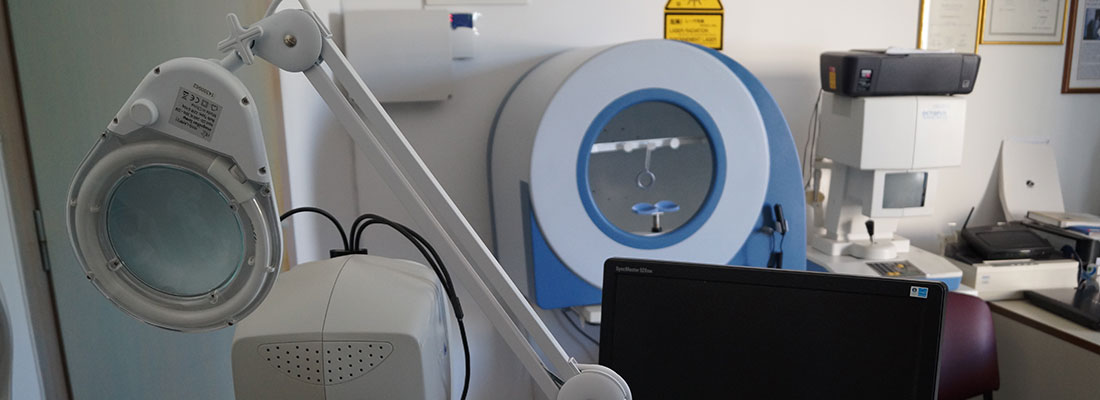

Διαθέτουμε σύγχρονα μηχανήματα για την διάγνωση και την παρακολούθηση παθήσεων ωχράς κηλίδος, γλαυκώματος κτλ.